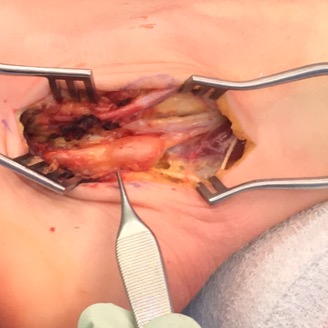

- local excision

Zhang et al J Foot Ankle Surg 2013

- surgical excision of 20 giant cell tumour tendon sheath foot & ankle

- recurrence rate 20%